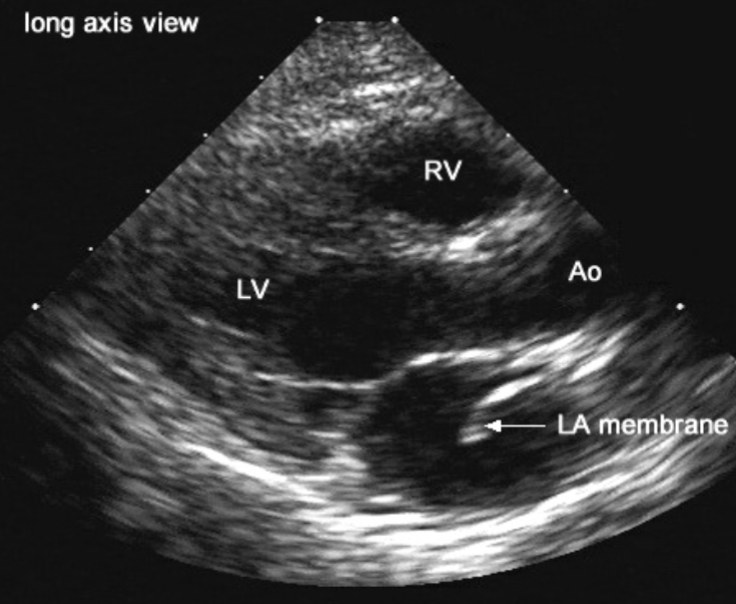

Cor Triatriatum

fibromuscular membranous partition

LA divided into 2 parts

Called “Sinister” or “Sinistrum”

Pulm venous return must pass through a false “chamber” / compartment posterior to the LA

membrane may have fenestrations

Diagnose obstruction of flow in the LV

mimics MS

Cor Triatriatum Sinister

associated w/:

ASD

PHTN

complications:

CHF

d/t increased pressure in LA and PA w/ MS

Cor Triatriatum Sinister 2D findings:

best views:

PLAX / A4C

see membrane within LA cavity